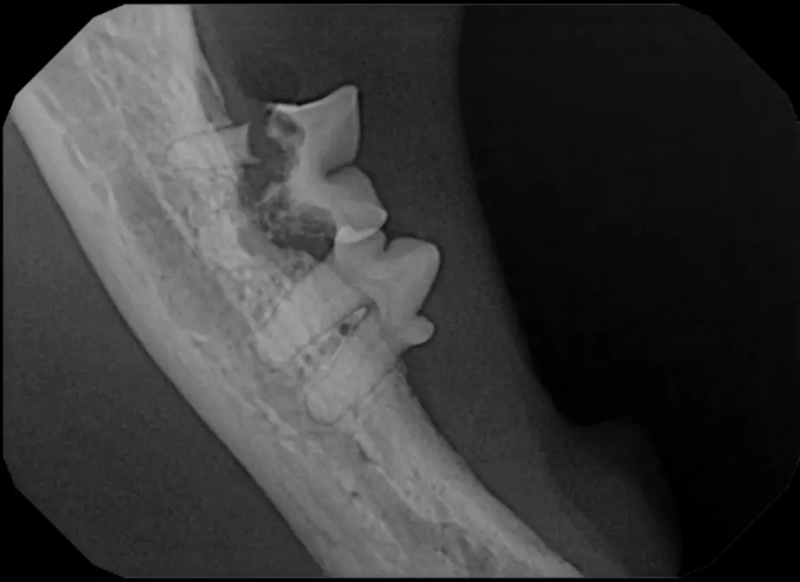

The Center now provides advanced imaging via cone beam CT. Cone beam CT is excellent for visualization of bony structures of the skull, nasal cavity, teeth, and ears. Cone beam CT is especially helpful for diagnosing dental disease and evaluation of jaw fractures. It can also be useful for evaluating the sinuses and tympanic bulla. Cone beam CT can be used in conjunction with nasal biopsy and culture to evaluate nasal discharge whether chronic or acute.

Pets can be involved in trauma that can cause fractures to their head, teeth, and jaw bones. Correctly repairing these fractures is extremely important for your pet to have normal function of their mouth. If a jaw fracture is allowed to heal in an abnormal position, your pet may have great difficulty chewing and can be in significant pain. Many fractures can be successfully treated with minimally invasive oral procedures, but more complicated cases may require bone plating techniques. The Center offers cone beam CT imaging which provides extremely detailed images of the bones of the head and skull. Advanced imaging with CBCT facilitates selection of the best surgical technique to get your pet back to eating and comfort as soon as possible.